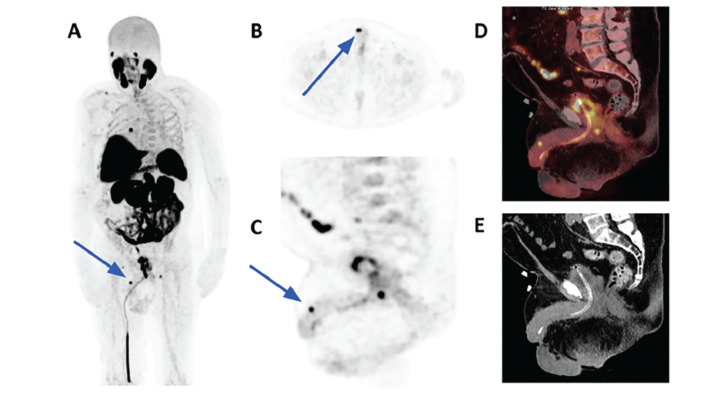

74岁男性,前列腺癌病史,前列腺特异性抗原升高,行18f -前列腺特异性膜抗原(PSMA)-1007正电子发射断层扫描/计算机断层扫描,以调查少转移性疾病。有证据表明,PSMA有盆腔和腹膜后淋巴结转移和骨骼沉积的局部复发表现。虽然罕见,容易被误认为是污染,但发现了一个小的阴茎转移。这与预后不良有关,并可能影响进一步的治疗。本病例强调了详细检查阴茎的重要性,以确保区分尿活动和病理性摄取。

A 74-year-old man with a history of prostate cancer and rising prostate-specific antigen underwent 18F-prostate specific membrane antigen PSMA)-1007 positron emission tomography/computed tomography for investigation of oligometastatic disease. There was evidence of PSMA avid local recurrence findings with pelvic and retroperitoneal nodal metastases and skeletal deposits. Although rare and could easily be mistaken for contamination, a small penile metastasis was found. This is associated with poor prognosis and could impact further management. This case highlights the importance of a detailed review of the penis, to ensure differentiation between urinary activity and pathological uptake.